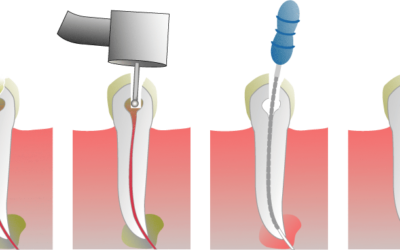

Les étapes de la dévitalisation dentaire